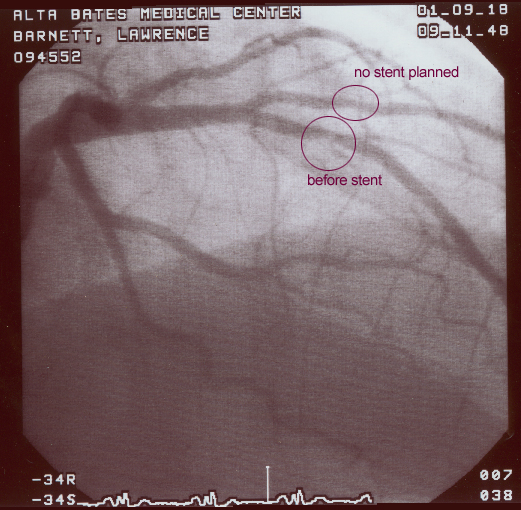

I learned to live with occasional irregularities in my heart rhythm, but in my late forties, those arrhythmias became problematic. Additional angiograms found that some arteries were becoming blocked. Angioplasty and a stent bought me more time. The recommendation was that I have an ICD implanted in my chest. I’m now on my fourth generation of ICD, an implanted heart defibrillator that also functions as a pacemaker.